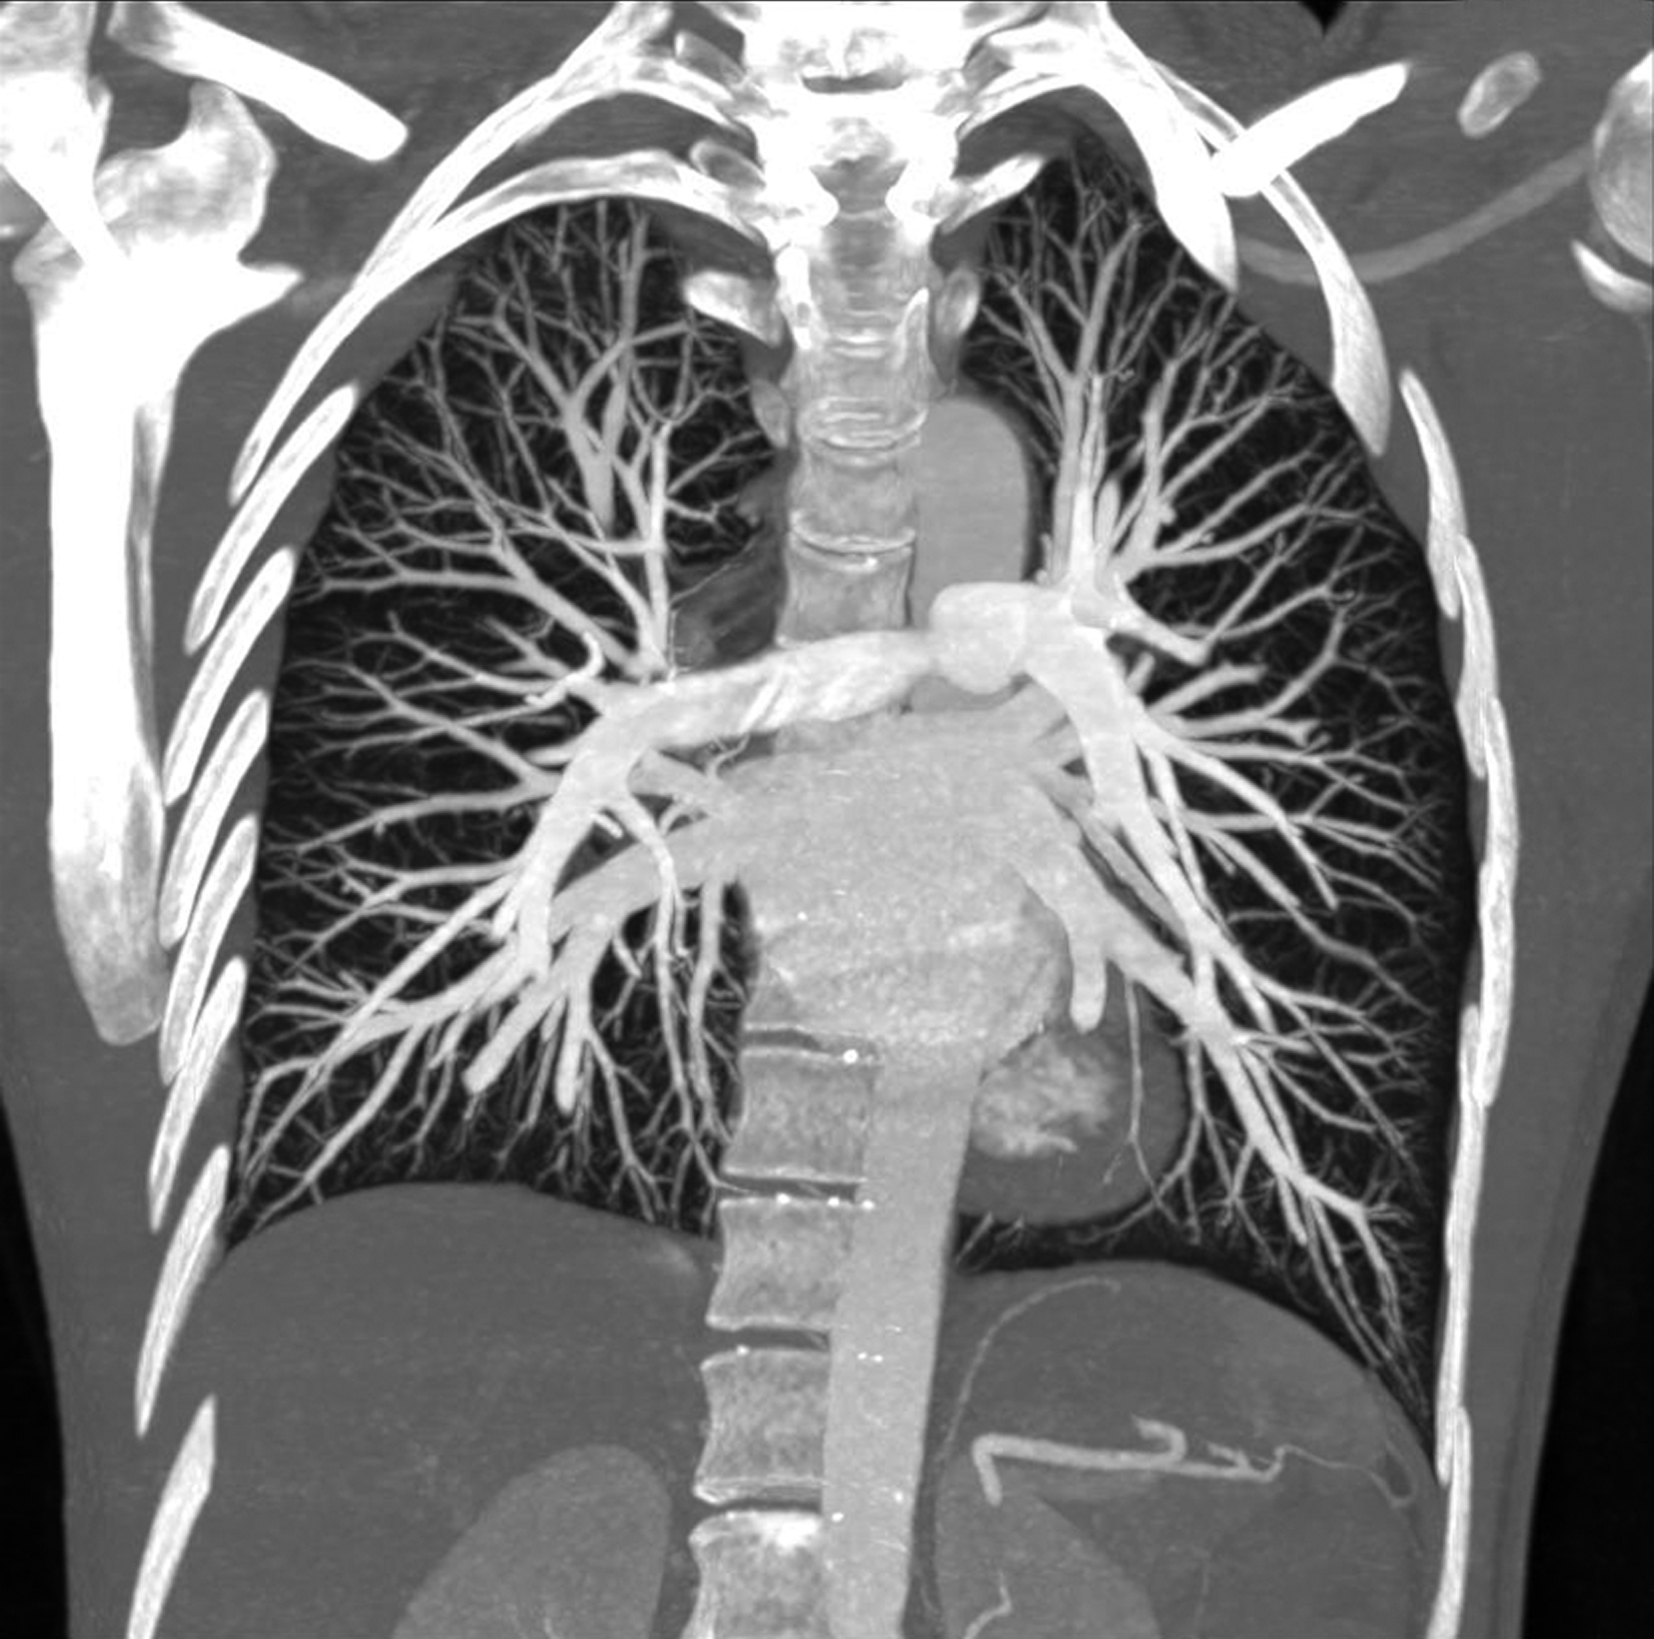

图8-1-4 常规肺动脉CT造影横断图及重建图像

图8-1-5 CTPA两期扫描应用:患者,男,37岁,二尖瓣狭窄,肺循环高压,怀疑肺栓塞。第一期右肺下叶基底段对比剂充盈不充分(ABC↑);第二期充盈充分(DEF↑),排除肺栓塞诊断